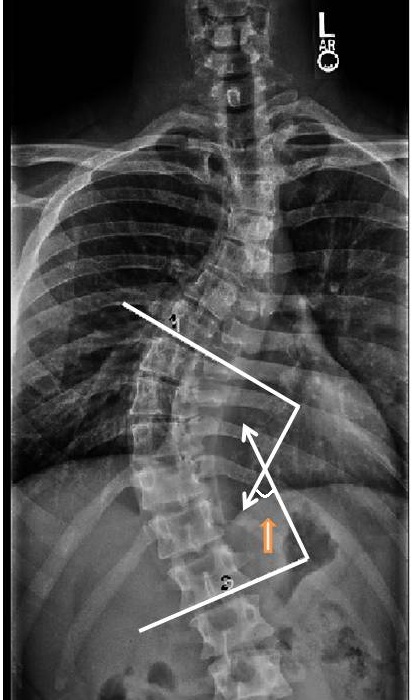

Using the AP view, identify the apex vertebra. Next, identify the end vertebra which have the maximally tilted end plate. Draw a line parallel to the superior and inferior end-plates of the upper and lower end vertebrae, respectively. The cobb angle is the angle between these lines.

how to draw the cobb angle